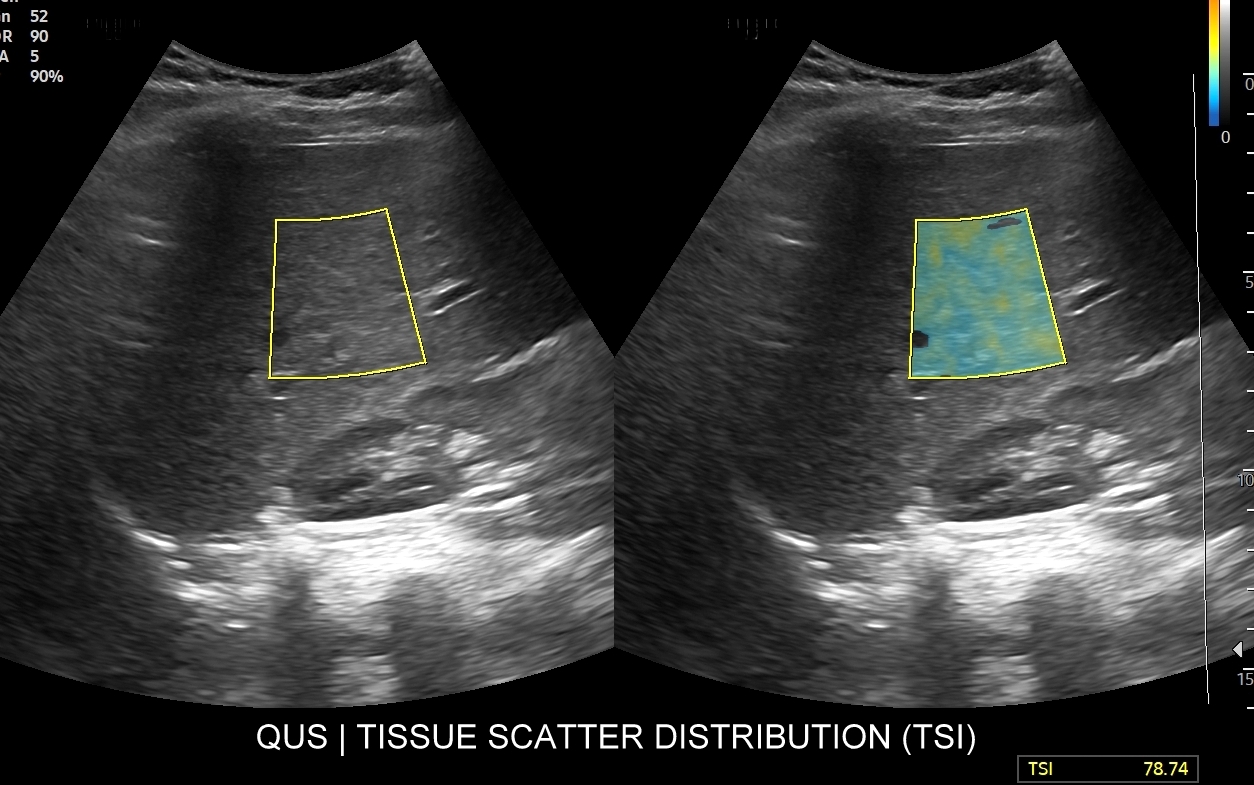

W ramach kompleksowej oceny wątroby elastografię 2D-SWE warto jednoczasowo połączyć z przeprowadzeniem badania USG przepływów wątrobowych oraz oceną stłuszczenia wątroby QUS w ramach kompleksowego badania MPUS brzucha. Podczas rejestracji zapytaj się o Multiparametryczne badanie USG / MPUS jamy brzusznej >